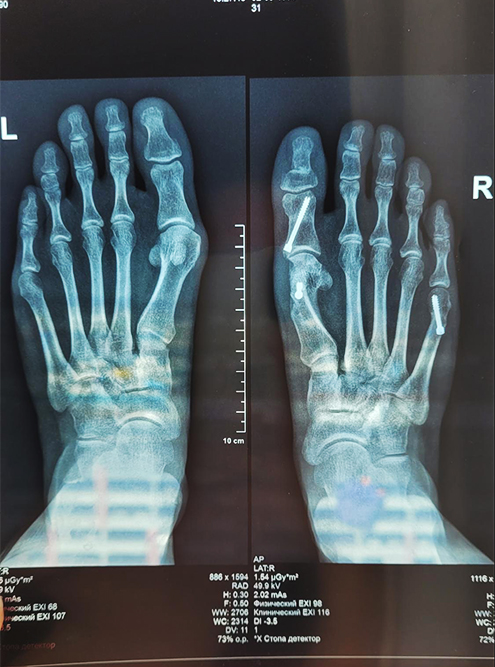

Медицинские решения: Операция по коррекции Hallux valgus